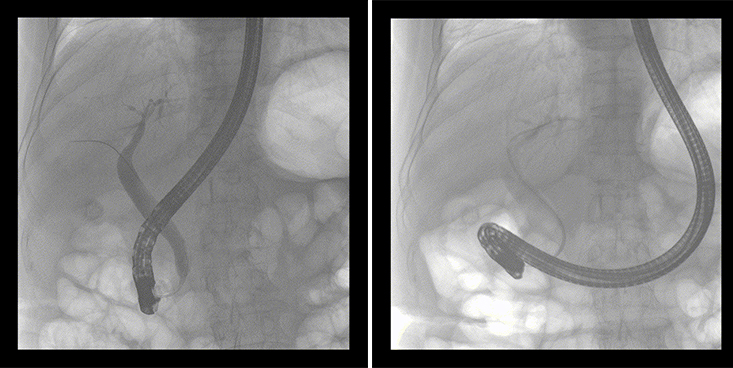

一位86歲的女性患者近來出現(xiàn)腹痛,入院后CT檢查并結(jié)合臨床表現(xiàn)被診斷為急性膽囊炎伴膽囊結(jié)石。經(jīng)專家團隊協(xié)商并與患者家屬溝通,決定對患者實施經(jīng)內(nèi)窺鏡逆行胰膽管造影(ERCP)。

ERCP(經(jīng)十二指腸鏡下逆行胰膽管造影)現(xiàn)已成為比較成熟的微創(chuàng)介入技術(shù),被廣泛的應(yīng)用于臨床,ERCP也是消化內(nèi)鏡領(lǐng)域難度大、風險大、技術(shù)復雜的微創(chuàng)手術(shù),其并發(fā)癥多為致命性,ERCP手術(shù)對醫(yī)生的要求很高,因此,ERCP醫(yī)生又被稱為“刀尖上的舞者”。因為手術(shù)難度較大,過程復雜,需要C形臂精準的配合,對影像清晰度的要求也非常高。

普愛醫(yī)療移動式平板中C為本次ERCP手術(shù)提供實時無損高清影像,幫助醫(yī)生精準定位。“成像效果非常棒!完全不輸國際大牌的醫(yī)學影像設(shè)備……”鼓樓醫(yī)院江北國際醫(yī)院內(nèi)鏡中心手術(shù)團隊對普愛醫(yī)療移動式平板中C的成像效果給與了高度的評價。

在消化內(nèi)科主任的領(lǐng)導和多科室全力配合下,南京鼓樓醫(yī)院江北國際醫(yī)院成功完成了首例ERCP手術(shù)。